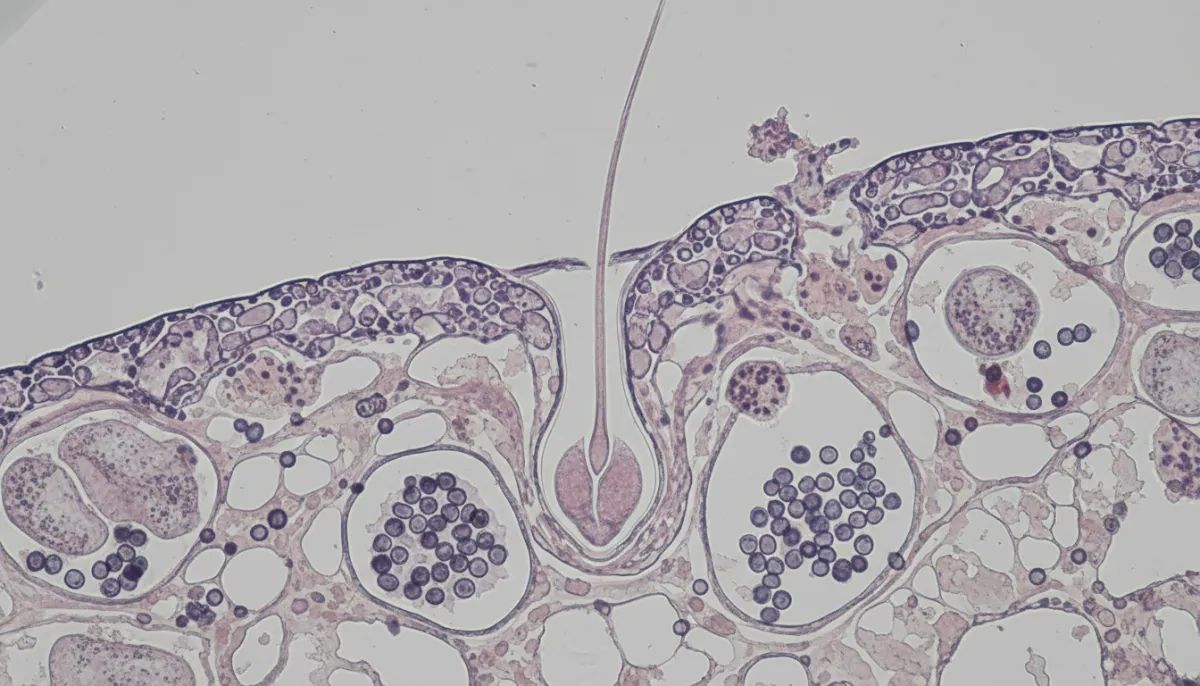

Steroids interact with hair follicles primarily through the androgen receptor pathway. When a steroid such as testosterone or a synthetic analogue binds to these receptors, it can accelerate the transition of thick, terminal hairs into finer, vellus hairs—a process known as follicular miniaturisation. This is the same mechanism that underlies male‑pattern baldness.

Research shows that elevated levels of dihydrotestosterone (DHT), a potent metabolite of testosterone, are closely associated with hair‑follicle shrinkage. Anabolic steroids increase systemic testosterone, which can be converted to DHT by the enzyme 5‑α‑reductase. Consequently, users may experience accelerated shedding, especially on the crown and frontal scalp.